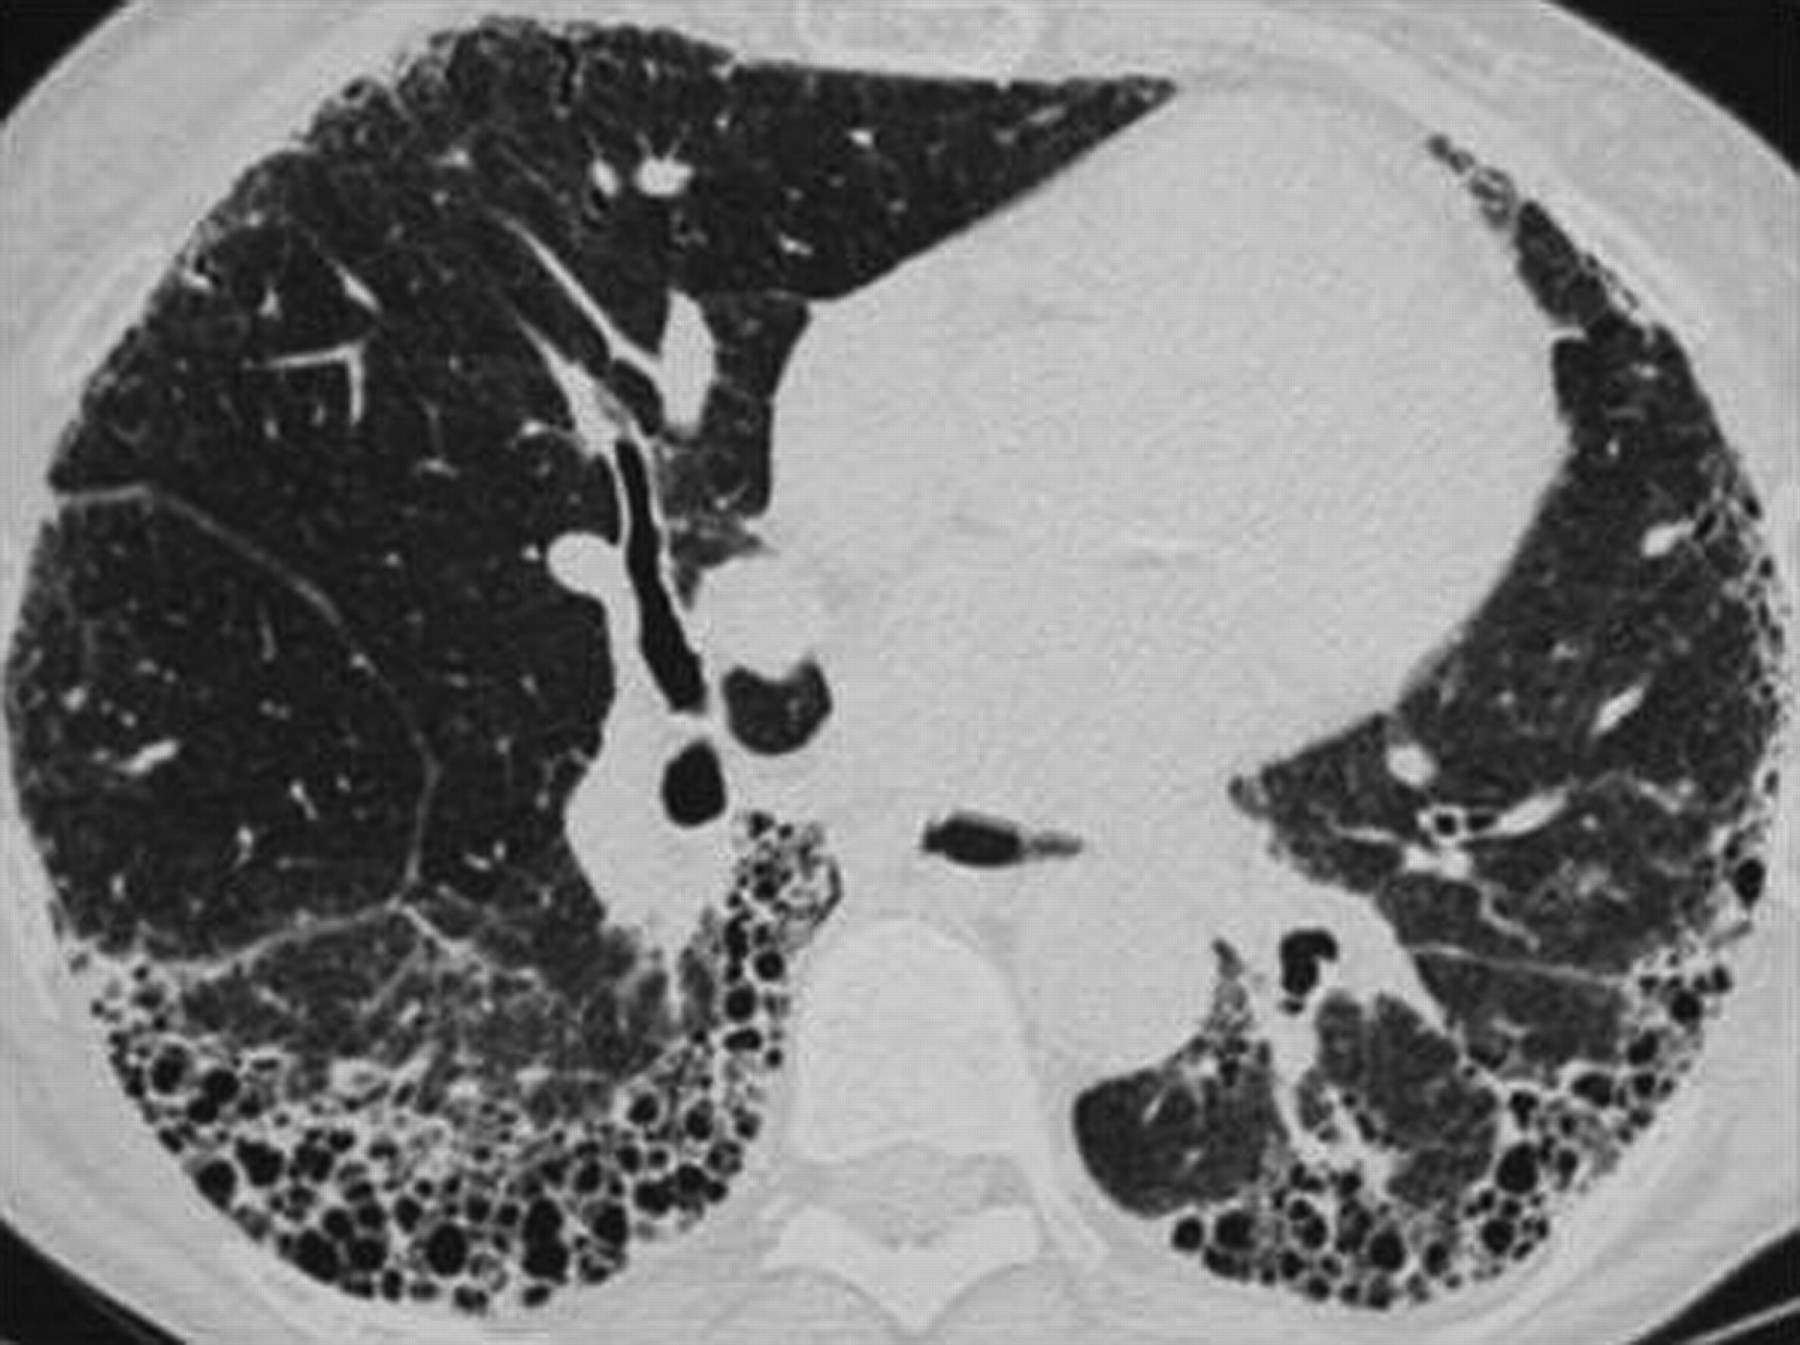

_特發性肺纖維化的高清CT圖像

_特發性肺纖維化ct表現圖